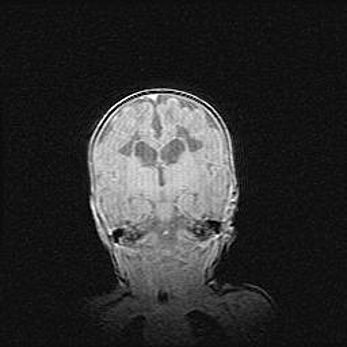

Лейкомаляция с кистозно-глиозной дегенерацией головного мозга.

Возраст: 2 месяца 25 дней

Вес: 6400 г

Окружность головы: 40 см

Срок гестации: 41 неделя

Лейкомаляцию относят к ишемически-гипоксическим повреждениям головного мозга, диагностируемым у новорожденных. При лейкомаляции в головном мозге обнаруживают очаги некроза, возникшие после тяжелой гипоксии и нарушения кровотока. В процессе морфогенеза очаги проходят три стадии: 1) развития некроза, 2) резорбции и 3) формирования глиозного рубца или кисты. Перивентрикулярная лейкомаляция (ПЛ) встречается примерно в 12% случаев среди новорожденных, обычно – у недоношенных детей, причем, частота ее зависит от массы, с которой младенец появился на свет. Наибольшее число малышей страдает лейкомаляцией, если масса при рождении 1500-2500 г.